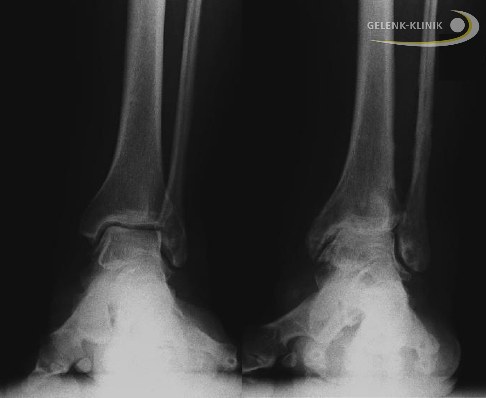

Üblicherweise werden vor der Behandlung mit einem Distraktionsfixateur verschiedene technische Untersuchungen notwendig. Belastete radiologische Untersuchungen helfen nicht nur bei der Analyse der Schädigung und der Therapieentscheidung. Sie ermöglichen auch, weitere Fehlstellungen zu erkennen, die vor einer Distraktionsarthroplastik begradigt werden sollten.

- Heute wird dafür vor allem die Digitale Volumentomographie (DVT) eingesetzt. Sie ermöglicht eine dreidimensionale Darstellung von Knochenanbauten (Osteophyten), subchondralen Knochenzysten (durch Druckbelastung im Rahmen der Arthrose entstandenen Hohlräumen) sowie von Fehlstellungen im Gelenk. Darüber hinaus können auch subchondrale (unter dem Knorpel liegende) Knochenveränderungen wie eine Sklerosierung (Verdichtung) der Knochenlamelle sichtbar gemacht und beurteilt werden. Die Methode dient nicht nur der Diagnosestellung, sondern ist auch im weiteren Verlauf einer Distraktionsarthroplastik zur Beurteilung des Heilungsprozesses von Nutzen.